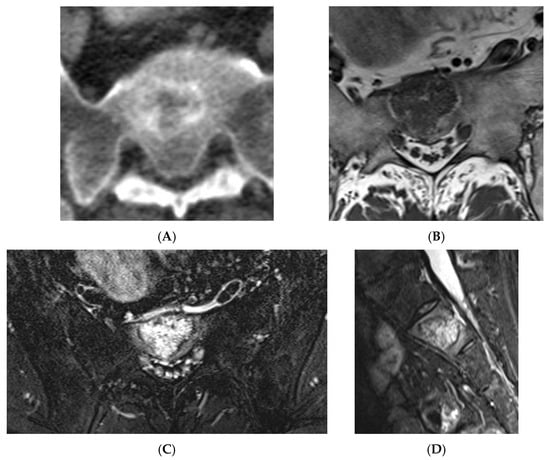

Atypical haemangioma at sacrum. (A) Axial CT. (B) T1W axial MRI. (C) Axial STIR MRI. (D) Sagittal STIR MRI.

Figure 12.